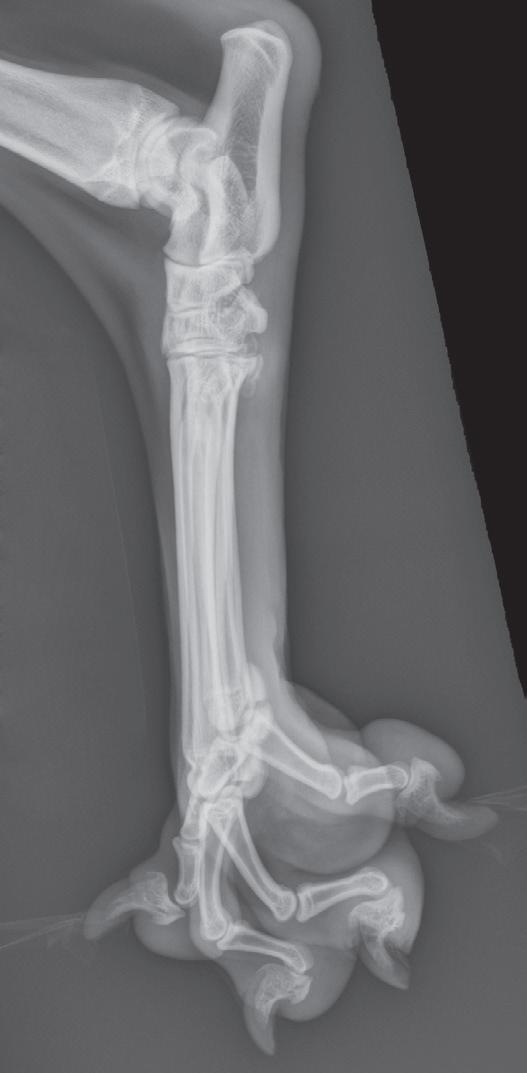

Figure 1-6. Dorsoventral (A), lateral (B), and rostrocaudal (C) radiographs of a box turtle. In A and B, which are orthogonal to each other, it is clear that the subject is a turtle. Eggs are visible in the coelom. In C, which is also an orthogonal view with respect to both A and B, it is not obvious that the subject is a turtle because this orientation is uncommon and unfamiliar. The eggs are also not visible in C.